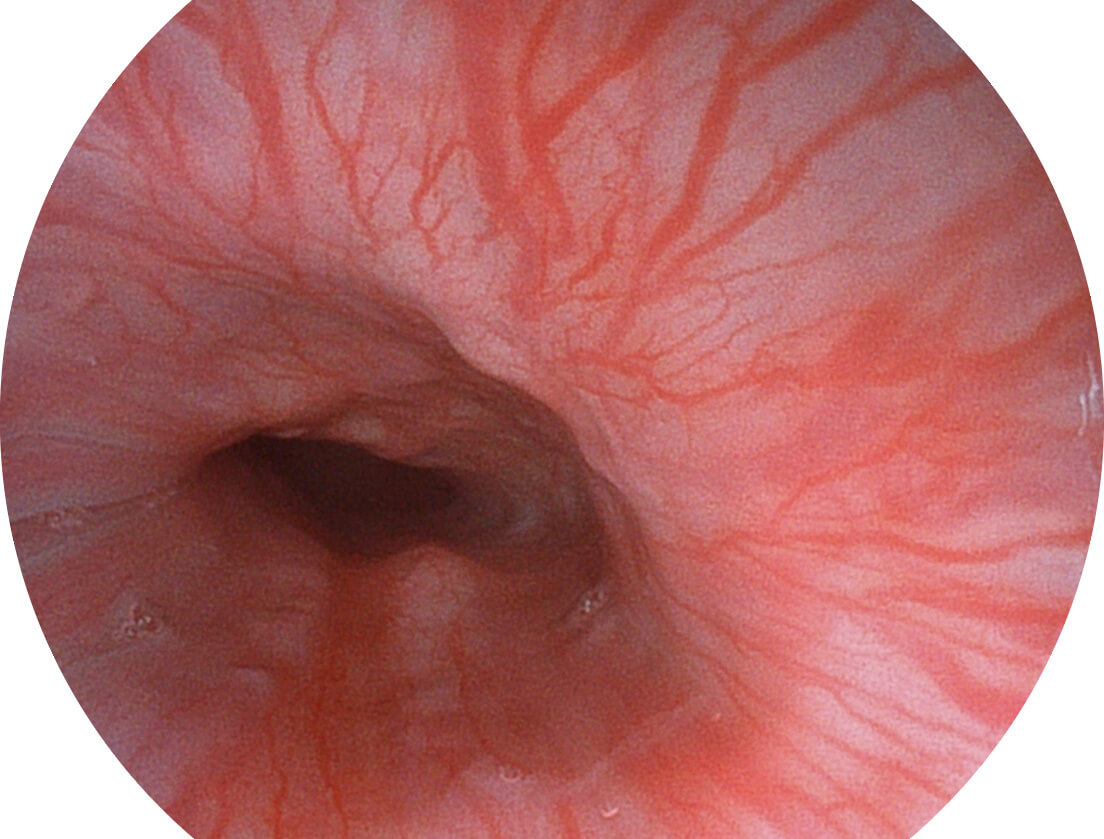

图像具有高亮度、高黏膜血管颜色对比度的特点,且不改变粘液、食物残渣、粪便的基本颜色,可在中远景下进行观察,助力消化道早期疾病的诊断。

采用光路合束技术,光谱自由度高,实现了更丰富的照明模式,染色模式SFI及VIST,从远景到近景,助力消化道早期疾病诊断。